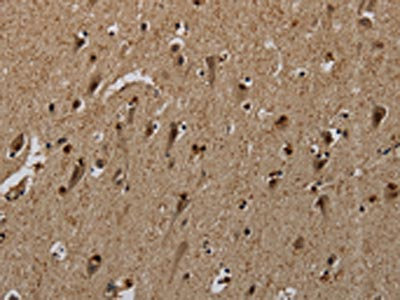

The image on the left is immunohistochemistry of paraffin-embedded Human brain tissue using CSB-PA184660(PNN Antibody) at dilution 1/50, on the right is treated with synthetic peptide. (Original magnification: ×200)